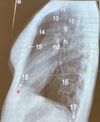

Que estructura anatómica esta en el numero 11

Traquea

41

Que estructura anatómica esta en el numero 13

Vasos supra aórticos

42

Que estructura anatómica esta en el numero 15

Espacio retro traqueal

43

Que estructura anatómica esta en el numero 9

Cayado aórtico

44

Que estructura anatómica esta en el numero 14

Espacio aéreo retro-esternal

45

Que estructura anatómica esta en el numero 19

Esternón

46

Que estructura anatómica esta en el numero 18

S.Cardiofrenico